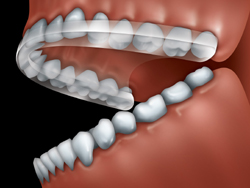

Your dentist may suggest wearing a night guard, also called an occlusal splint. It is made of clear plastic and fits over the biting surfaces of the teeth of one jaw so that you bite against the splint rather than your teeth. This often helps your jaw joints and muscles to relax.

An occlusal splint is made of plastic and fits

over the biting surfaces of the teeth of one jaw.